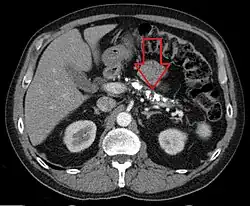

Die erste klare Beschreibung der pathologischen Anatomie der chronischen Pankreatitis stammt von Ch. Dieckhoff (1894).[26] Pankreasverkalkungen werden durch Ultraschall, Röntgenaufnahme des Oberbauches, Computertomografie oder Magnetresonanztomographie nachgewiesen und beweisen eine chronische Pankreatitis. Pankreasgangsteine werden mit der Endoskopisch retrograden Cholangiopankreatikographie bildlich dargestellt.